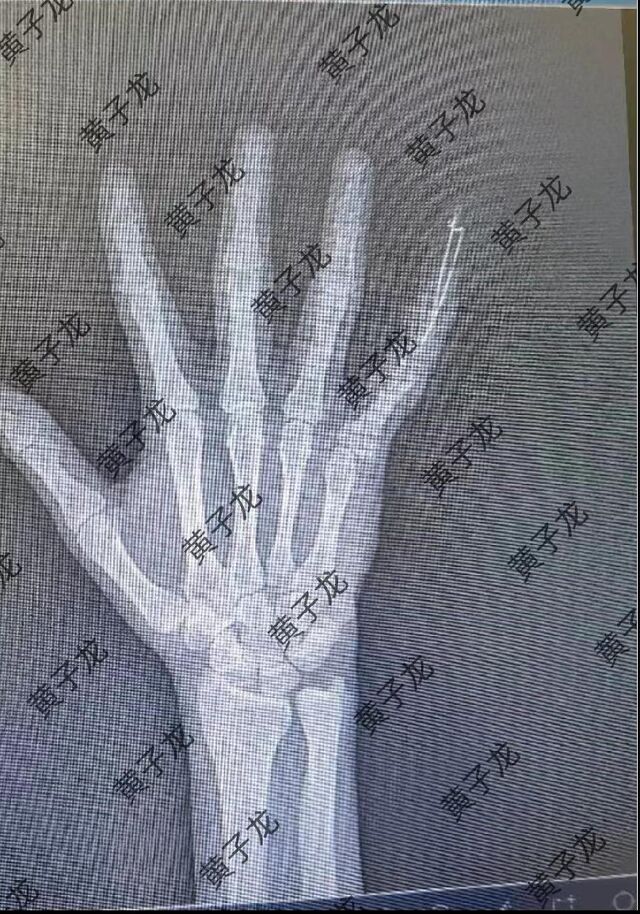

[修复重建] 小指伸肌腱止点撕脱性陈旧性骨折

陈旧性骨折近一个月,来我院就诊。我采用切开复位阻挡法,效果满意! 图片1.png 图片2.png 图片3.png 图片4.png 图片5.png 图片6.png 图片7.png

术后6周